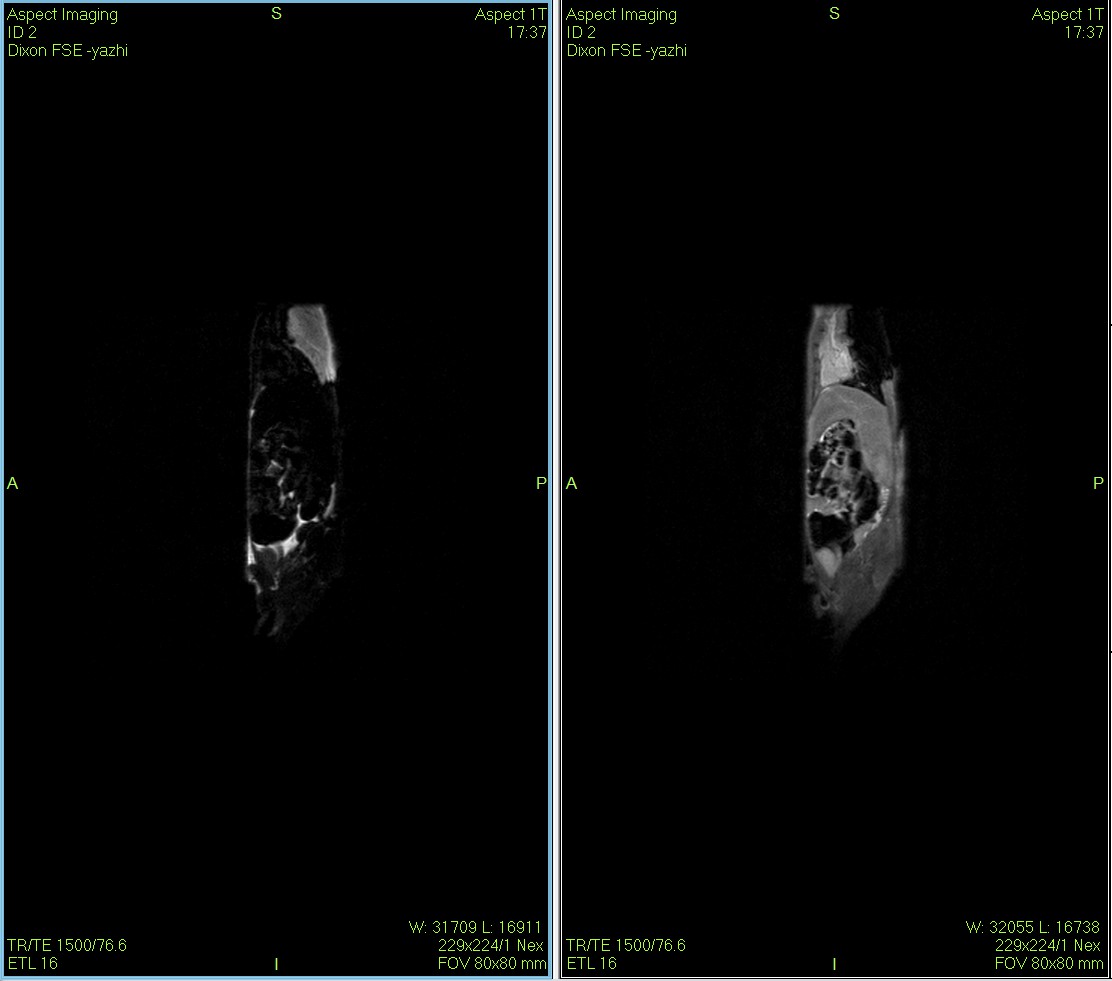

Dixon序列用于大鼠、小鼠水脂分离磁共振成像-脂肪抑制技术

Dixon脂肪抑制技术是由Dixon 提出,其基本原理是利用水、脂肪的化学位移差异,使用不同的回波时问,分别采集水和脂肪质子的in Phase 和 opposed -phase两种回波信号。